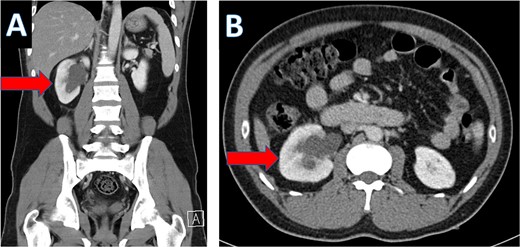

An IV contrast-enhanced CT scan of the abdomen and pelvis revealed an 8-mm proximal to mid-ureteral obstructive stone on the right side (Fig. 1), causing severe hydronephrosis of the right kidney and proximal hydroureter (Fig. 2).

CT scan showing right ureteral calculus (A: coronal; B: axial).